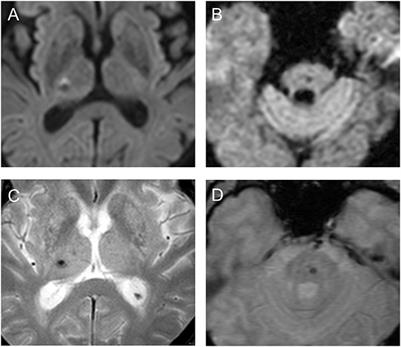

Original Research

Published on 08 Nov 2022

in Applied Neuroimaging